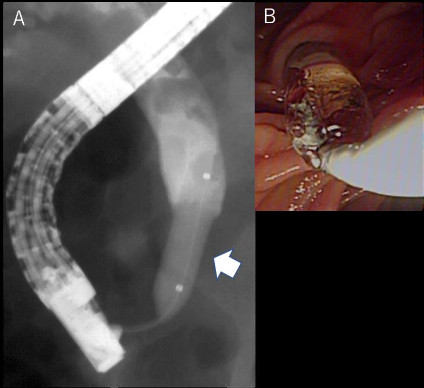

図1 内視鏡的乳頭バルーン拡張術(EPBD).

A; 透視画像。矢印がEPBDバルーン。総胆管内には多数の結石が指摘できる。

B; 内視鏡画像。乳頭はバルーン拡張されている。